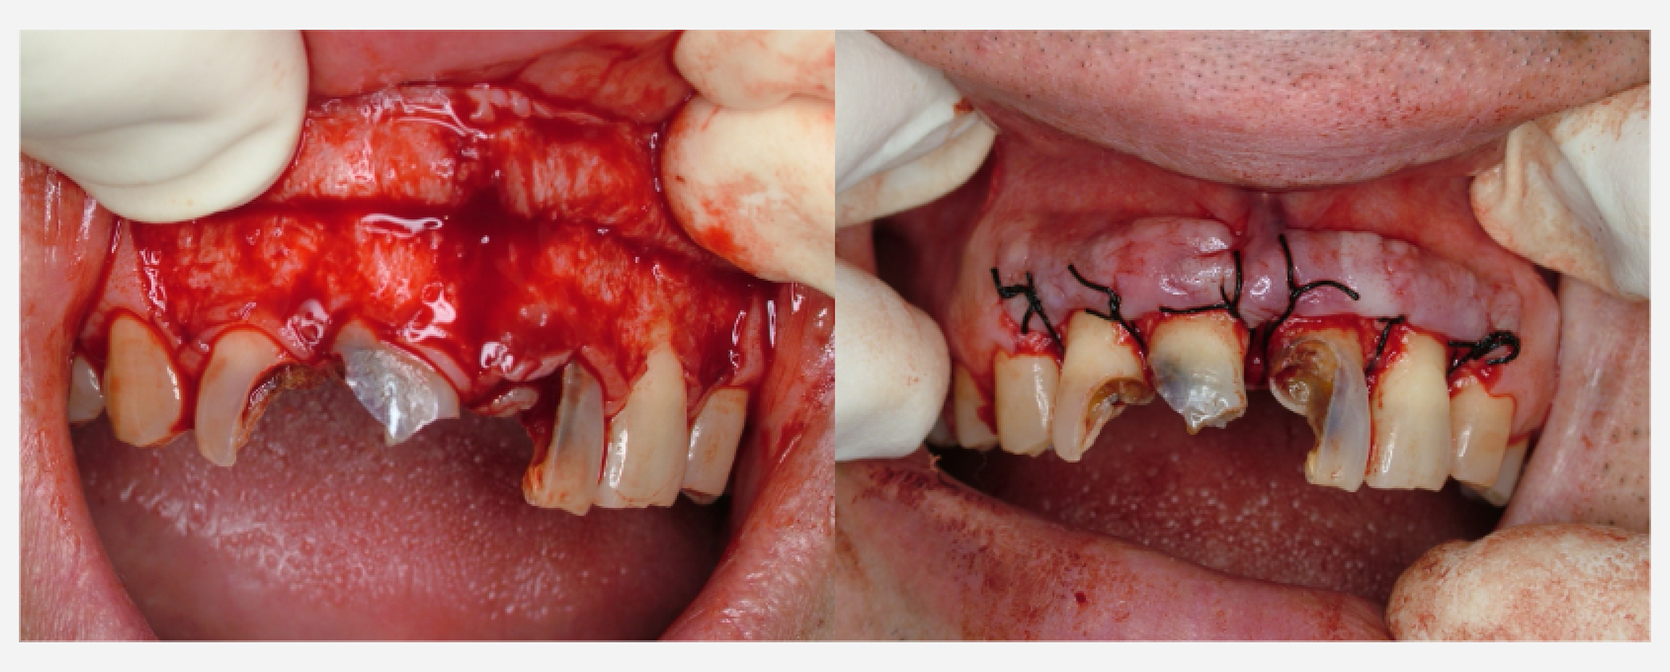

治療前

治療経過

術後3ヶ月 仮歯装着

術後1年後

治療前と治療後

| 治療内容 | 歯周外科:歯肉弁根尖側移動術 (Apically Positioned Flap Operation) |

|---|---|

| 患者様の年齢 | 35歳 |

| 患者様の性別 | 男性 |

| 治療期間 | 初診時より2年 |

| 治療回数 | 矯正治療合わせて85回程度 |

| 治療費用 | インプラント:150万円/歯周外科:3万円/補綴治療:50万円 |

| 治療で得られるメリット |

|

| 治療する際に起こる リスク・副作用 |